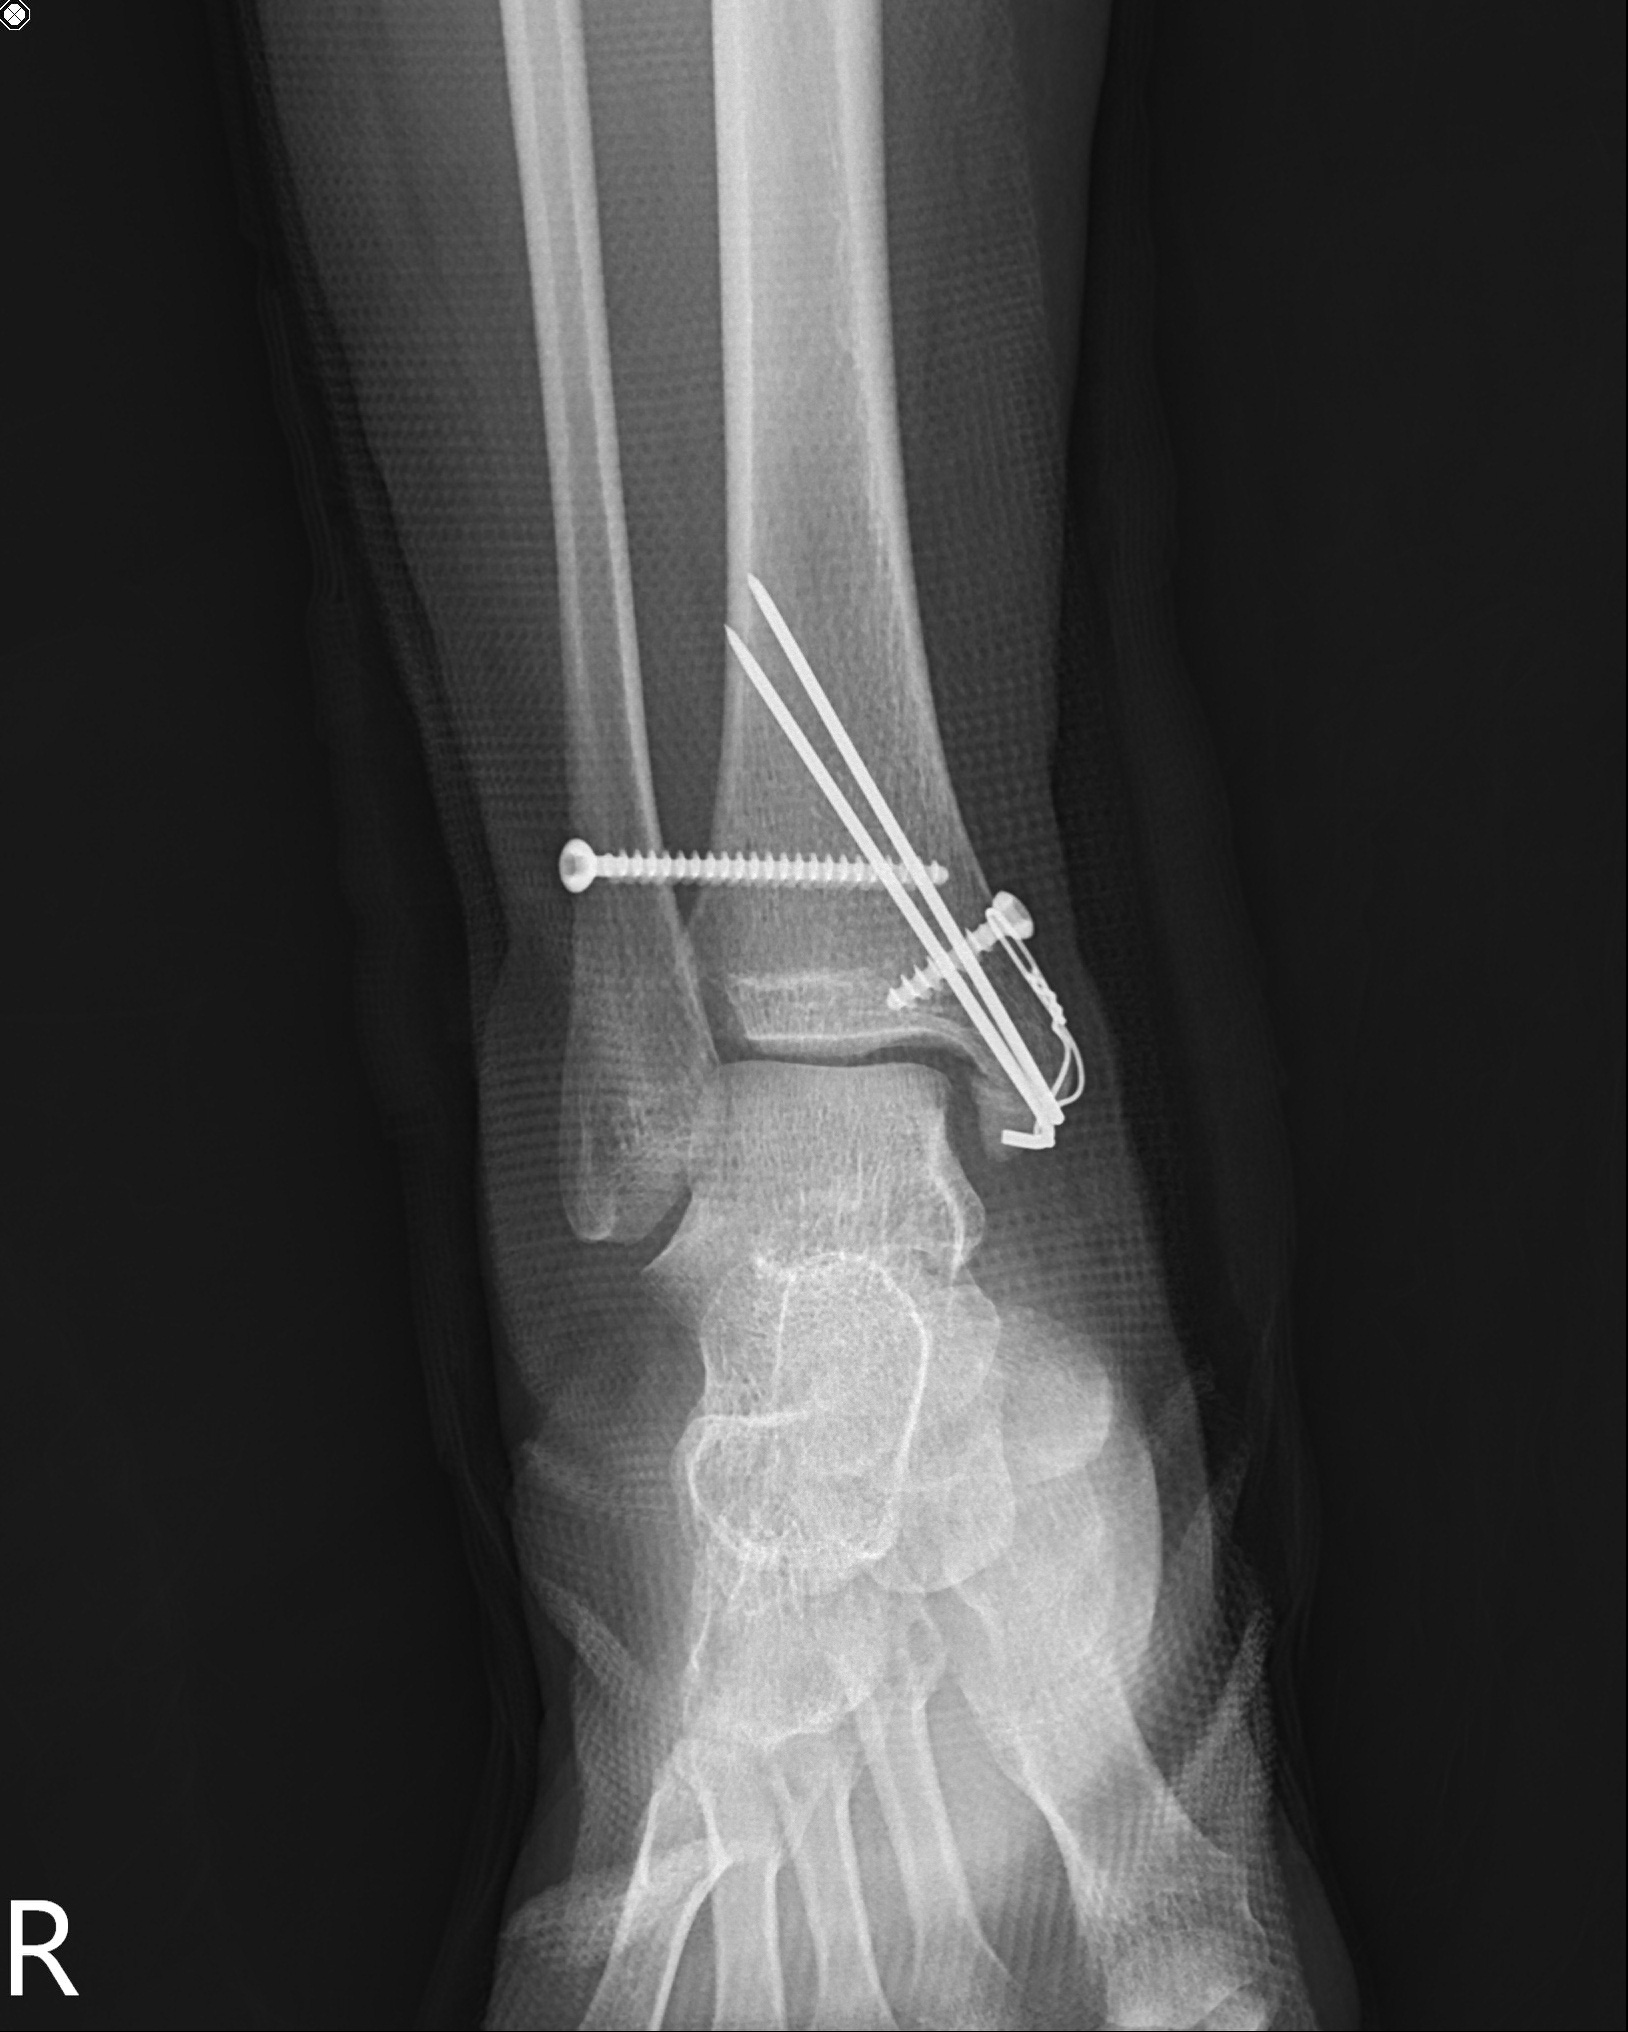

Maisonneuve fracture(메종누보 골절)

26 years old female patient

Post-op

Product : 1.6 k-wires, 4.0 mm cancellous screw

medial malleolar low transverse Fx는

꼭 k-wires & tension band wiring을 해야한다